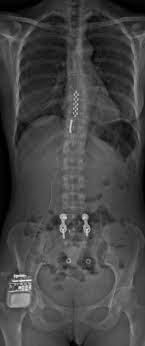

Neurostimulation médullaire :

- Définition : Intervention chirurgicale permettant le traitement des douleurs neuropathiques chroniques chez des patients en échec de traitements chirurgicaux et médicamenteux.

- But : Soulager les douleurs neuropathiques chroniques.

- Principe : intervention chirurgicale en deux temps :